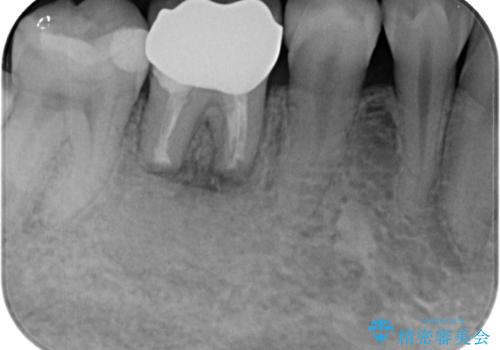

右下奥歯は既に根管治療が行われており、セラミッククラウンが装着されていました。

セラミッククラウンを壊して再度根管治療を行い、その後セラミッククラウンを装着する方法か、外科的に歯根の先端を切除し、炎症の原因である細菌を取り除き治癒を図る方法とを提案し、極力クラウンを壊さずに治療を進めたいとの希望により、歯根端切除術を行うこととしました。

治療から9か月ほどが経過した時点で、違和感や痛みはなく、歯根端切除術を行った右下は、レントゲンでも良好な経過が確認できました。